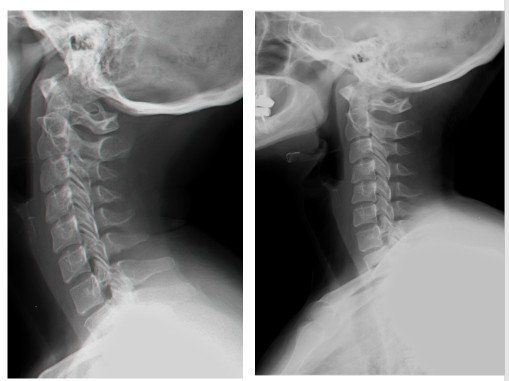

ื"ืจ ื ืืืื ืงืืืข ืืช ืชืืื ืืช ืืืืคืื ืืืืืืฆืช ืืืชืื ืืืกืืืจืื ืืจืคืืืืช, ืืืฆืื ืืืืืงืืช, ืืืฆืื ืจื ืืื, ืกื-ืื ืื ืื-ืืจ-ืืื, ืืืฉืืฉ ืืืืืืช ืืืืืืจ ืฉื ืคืืข ืืืืืื ืืืจืืคืจืงืื ืืื ืืืขืจืื ืขื ืืื ืืฉืคืืข ืื ืืง ืืขืืื ืืฉืืืจื ืขื ืืขืจืืช ืืขืฆืืื ืืืจืืืืช ืืืืฃ. ืืฉืื ืืืืืจ ืฉืชืคืงืื ืืืืจืืคืจืงื ืืื ืืืกืืจ ืกืืืืงืกืฆืื (ืชืช ื ืงืืขื ืฉืืจืชื) ืฉืืคืจืืข ืืืืฃ ืืชืคืงื ืืืืคื ืืืคืืืืื. ืชืืืื ืจืืคืื ืืจืงืืืช ืืื ืืืขื ืืืชืืคืฉืจ ืืชืื ืืืืฃ ืขืฆืื. ืืืืฃ ืืฉ ืืืืืช ืจืืคืื ืืืขืืช ืืืืืืขืช ืืืจืงื ืืื ืื ืืฉืื. ืืืืืื ืืืืจืืคืจืงืื ืืกืืจ ืืืฅ ืืืืขืจืืช ืืขืฆืืืช ืข"ื ืฉืืคืืจ ืชืคืงืื ืขืืื ืืฉืืจื, ืืืืคืฉืจ ืืื ืจืืื ืืขืฆืืืช ืืืฉืชืืฉ ืืืืืืืช ืืืืฃ ืืืืขืืืช ืืืืืื. ืจืคืืื ืืืชืืช ืชืืื ืืื ืืืื ืืืืื ืืชืื ืืืืฃ ืขืฆืื. ืชืงืฉืืจืช ืืื ืืืื ืืืืฃ ืืืืจื ืืื ืืืืฃ ืืืื ืืืื ืืช ืืงืืื ืืืืฃ ืืืจืืืืชื. ืคืืื ืฆืืื ืืืจืืืืช ืืืืืช ืื ืจืืืืช ืืืืื ืฉืืืืฃ ืืืื ืืืืืข ืชืืืืื ืืืจืืืืช ืขืืื ืืฉืืจื ืืืืขืจืืช ืืขืฆืืืช ืฉืคืืขืืื ืืื ืืคืจืขืืช ืืืชืืื.

ืืืืคืื ืืืืจืืคืจืงืื ืืืื ืืช ืืืืฃ ืืืืจืืฅ ืืช ืื ืจืืืืช ืืืืื ืืชืืื ืืืืืื.